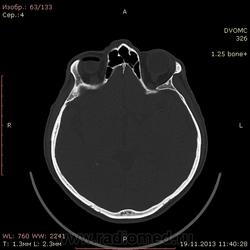

49 лет. Травма около месяца назад - удар в верхнюю челюсть спереди, так сказать...под нос.... в субнозальную область:-) Жалобы только на небольшие боли в месте травмы.

Воздух в правой орбите - под веком или нет? При моргании мог он так туда попасть и так распределиться? Или в резутьтате травмы из пазухи как-то попал и не уходит?

Мелкие пузырьки воздуха попадались, но такое количество и в виде кольца...Это нормально?